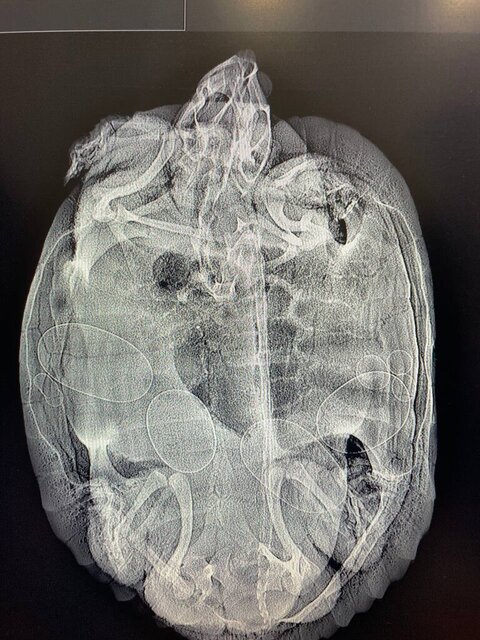

Ранее были в ветклинике "Птицыных" летом, у врача Птицына, делали рентген (приложу фото) после этого черепаха 2 раза яички снесла в воде в коробке не захотела. Больше рентген не делали.

Ренгент (делали летом) telegram-cloud-photo-size-2-5314686076914358396-y.thumb.jpg.98b219490c4fa0abd65cffbf0f2bde2b.jpg